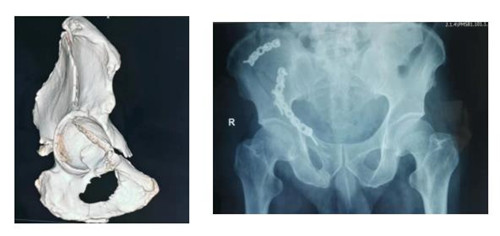

10月5日,MILAN.COM骨三科收住一位不同寻常的患者。该患者自1.5米高处坠落,右髋部着地,致右髋部持续剧烈疼痛,不能行走站立,被他人救起送往就近医院。行X线、CT检查示:右髂骨、髋臼、耻骨升降支多发骨折。因手术难度较大,患者家属辗转渭南各医院,经多方打听胡洪波副主任医师在骨盆髋臼骨折治疗方面颇有经验,特前来我院。

接诊该病人后胡洪波副主任前往CT室对骨折移位情况进行分析、定位。经过详细询问病史、查体,结合检查结果,骨三科团队确定采用经腹旁外侧入路为患者进行手术。手术耗时短,出血少,骨折复位满意,固定可靠,患者和家属对治疗效果十分满意。

骨盆髋臼骨折腹旁外侧入路也是胡洪波副主任在骨盆髋臼骨折领域继stoppa入路之后带来了第二个新的手术入路。腹旁外侧入路是进行髋臼前柱骨折的新的手术入路方式,此入路临近血管、神经、腹膜等重要器管,所以临床中还未能广泛开展。但因为此入路具有切口小、创伤少、患者恢复快等巨大优点,近年来已逐渐应用于临床,为骨盆髋臼骨折患者的快速康复带来了福音。